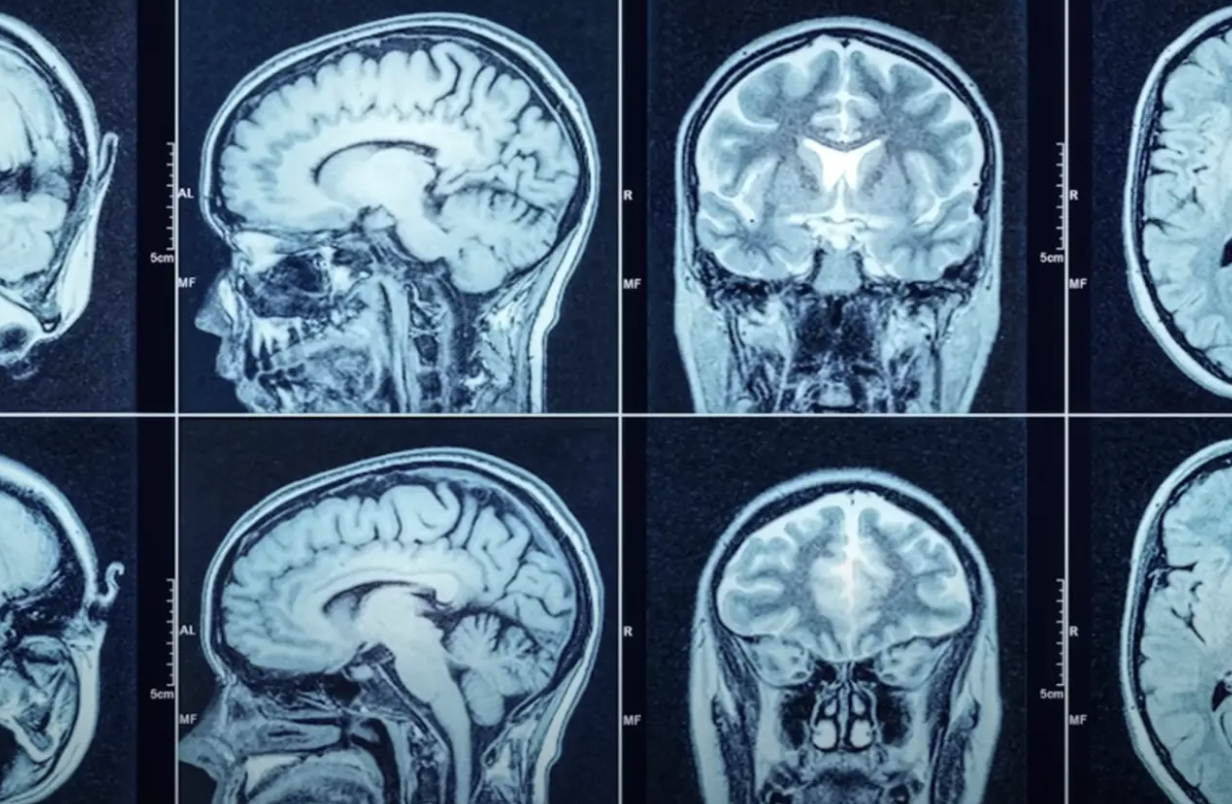

“Hvis du nogensinde har kigget på en MR-scanning af en person med multipel sklerose, er der noget, der kaldes hvide stofsygdomme,” siger han.

“MRI-scanningen viser en stor mængde hvidt væv i hele hjernen. Dette er tegn på skader forårsaget af immunsystemet, der angriber hjernen.”

“Man kan ret hurtigt se, at der er noget galt.”